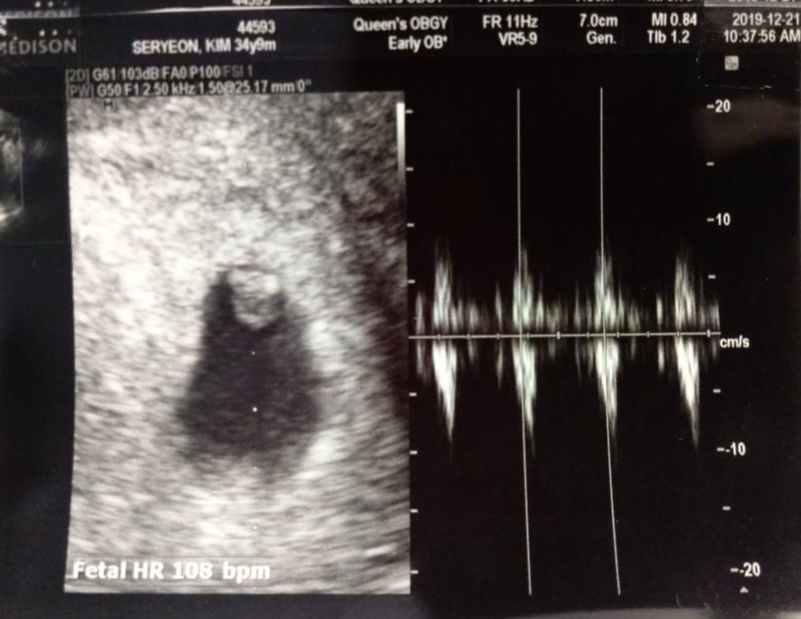

임신 6주차에 B-초음파 검사를 하러 병원에 갔는데 임신 6주차에 아기집이 있었는데 태아가 내부가 굉장히 작아보이고 심장박동소리가 들린다고 하더군요. , 하지만 그는 자신의 심장 박동을 들었을 때 매우 감동했다고 말했습니다.

지금까지 임신 6주차 증상인 심장초음파를 작성해보았습니다.